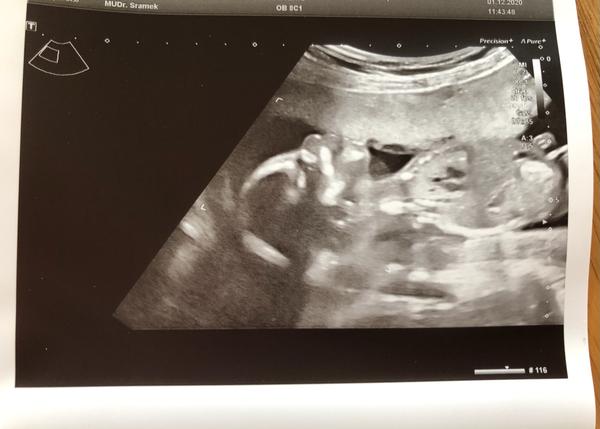

Poznáte pohlaví miminka podle utz z 1. i 2. trimestru?

Ahoj holky, jsem tu nová tak nevím moc jak to tu funguje. Poznáte podle ultrazvuku z 1. i 2. trimestru o jaké pohlaví se jedna? Můj doktor mi oznámil, ze mi nic ani nenaznaci pokud si nebude jistý alespoň na 90 % 🤷🏻♀️

Já bych řekla holcicka. Pohlavní hrbolek je spíše rovnoběžné s páteří. Já teď cekam 3ti holčičku (potvrzeno genetikou) a uz byl hodně podobný. Nemám ale foto.